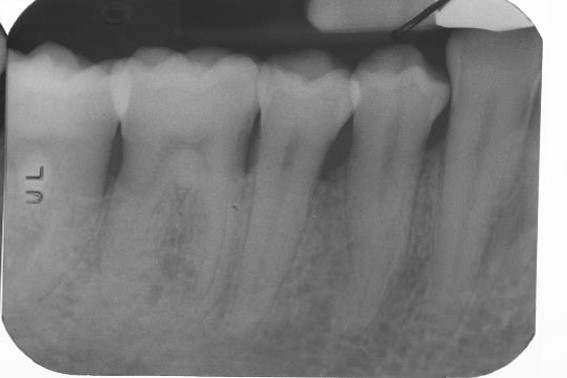

Radiographic view before periodontal regenerative therapy with Straumann® Emdogain®. A deep intrabony defect appeared mesially and distally on the left mandibular first premolar. Pre-surgical probing measured 8 mm. The defect morphology presented as well-contained.